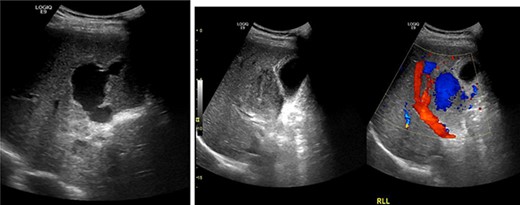

Resuscitation was carried on with 2 l of normal saline and two PRBC units to stabilize the patient. The computed tomography (CT) scan identified Grade 4 liver injury with hemoperitoneum (Fig. 2). Subsequently, the multiple bone fractures underwent surgical fixation, and post-operatively, he was hemodynamically stable. On the fifth day after admission, repeated CT scan demonstrated the liver injury with no evidence of hepatic pseudoaneurysm (Fig. 3). The patient remained stable with tolerated feeding with no abdominal pain or distension. On the Day 17, he developed abdominal pain mainly in the epigastrium, which was associated with nausea and deep epigastric tenderness. Abdominal ultrasound (US) (Fig. 4) and CT scan (Fig. 5) revealed complex, large intraparenchymal hepatic pseudoaneurysm (measuring about 58 × 41 × 30 mm) related to the left hepatic artery Segment 4 branch with surrounding hematoma located mainly at segment 4B/A ,and there was another tiny pseudoaneurysm seen at Segment 4A. Selective angiography confirmed the diagnosis of pseudoaneurysm with multiple blood supplies from Segment IV and Segment II.

The diagnosis of hepatic artery aneurysm is made with either conventional angiography, CT-angiography or Doppler US [5]. On CT imaging, hepatic artery pseudoaneurysm is identified as a well-defined focal lesion of high attenuation with the same contrast enhancement as arterial structures [5]. In our case, hepatic artery pseudoaneurysm diagnosis was established with abdominal CT scan and was confirmed with hepatic angiography. Like the management of blunt splenic trauma in adults, the treatment of post-traumatic liver injury remains controversial. Some physicians believe that routine follow-up imaging is necessary in all cases of post-traumatic liver pseudoaneurysm because of the risk of disastrous hemorrhage, while others believe that they can simply be observed as spontaneous resolution is known to occur.